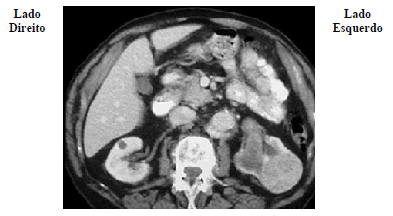

Um paciente de 65 anos de idade compareceu ao urologista por apresentar hematúria macroscópica, emagrecimento de 5 kg em dois meses e dor abdominal. Ao exame físico, o médico encontrou uma massa abdominal palpável em região de flanco esquerdo. Solicitou então uma tomografia computadorizada de abdome, demonstrada nessa imagem.

Com base nesse caso clínico e nos conhecimentos médicos correlatos, julgue o item a seguir.